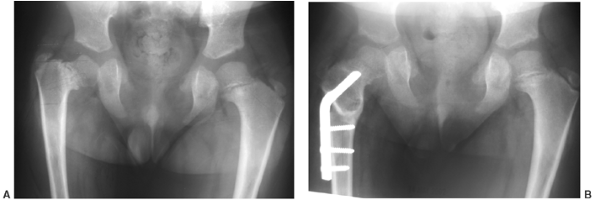

knee valgus is usually relatively symmetric. It results partially from

being underdeveloped (Fig. 8.14). An exostosis

may arise medially from the proximal tibial metaphy-sis. The acetabulae

the cardiac status is stable, is usually successful. The angular and

rotational disturbance of the lower extremities is usually addressed

when it becomes clinically significant or is rapidly progressing,

usually at approximately 20 degrees of valgus (80).

Bracing seems to have little or no effect, and surgery remains the

mainstay of treatment. Careful preoperative planning is needed, taking

into account deformity at all locations from the proximal femur to the

ankle, and aiming to correct the mechanical axes and the malrotation

with as few procedures as possible (81).

Usually, external fixation is the most effective way of performing the

correction. If the deformity is one of simple valgus, medial

hemiepiphyseal stapling alone may be adequate. If the wedging of the

lateral proximal tibial epiphysis is severe, elevation of the lateral

plateau may be necessary in a manner similar to medial elevation for

Blount disease. Limb lengthening is possible in this condition with a

minimum of complications.